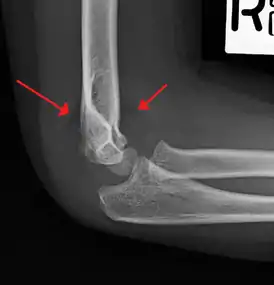

Supracondylar humerus fracture

| An elbow X-ray showing a displaced supracondylar fracture in a young child | |

A supracondylar humerus fracture is a fracture of the distal humerus just above the elbow joint. The fracture is usually transverse or oblique and above the medial and lateral condyles and epicondyles. This fracture pattern is relatively rare in adults, but is the most common type of elbow fracture in children.[1] In children, many of these fractures are non-displaced and can be treated with casting. Some are angulated or displaced and are best treated with surgery. In children, most of these fractures can be treated effectively with expectation for full recovery.[2] Some of these injuries can be complicated by poor healing or by associated blood vessel or nerve injuries with serious complications.

A supracondylar humerus facture is diagnosed by x-ray and the injured limb will be examined to assess the surrounding soft tissue, neurovascular status, and to identify any other injuries to the affected area.[5] Pain, swelling, and deformity near the elbow or arm area is common and a bleed near the fracture may result in an effusion in the elbow joint. With severe displacement, there may be an anterior dimple from the proximal bone end trapped within the biceps muscle. The skin is usually intact. If there is a laceration that communicates with the fracture site, it is an open fracture, which increases infection risk. For fractures with significant displacement, the bone end can be trapped within the biceps muscle with resulting tension producing an indentation to the skin, which is called a "pucker sign".

X-rays

Diagnosis is confirmed by x-ray imaging. Antero-posterior (AP) and lateral view of the elbow joint should be obtained. Any other sites of pain, deformity, or tenderness should warrant an X-ray for that area too. X-ray of the forearm (AP and lateral) should also be obtained for because of the common association of supracondylar fractures with the fractures of the forearm. Ideally, splintage should be used to immobilise the elbow at 20 to 30 degrees flexion in order to prevent further injury of the blood vessels and nerves while doing X-rays. Splinting of fracture site with full flexion or extension of the elbow is not recommended as it can stretch the blood vessels and nerves over the bone fragments or can cause impingement of these structures into the fracture site.[3]